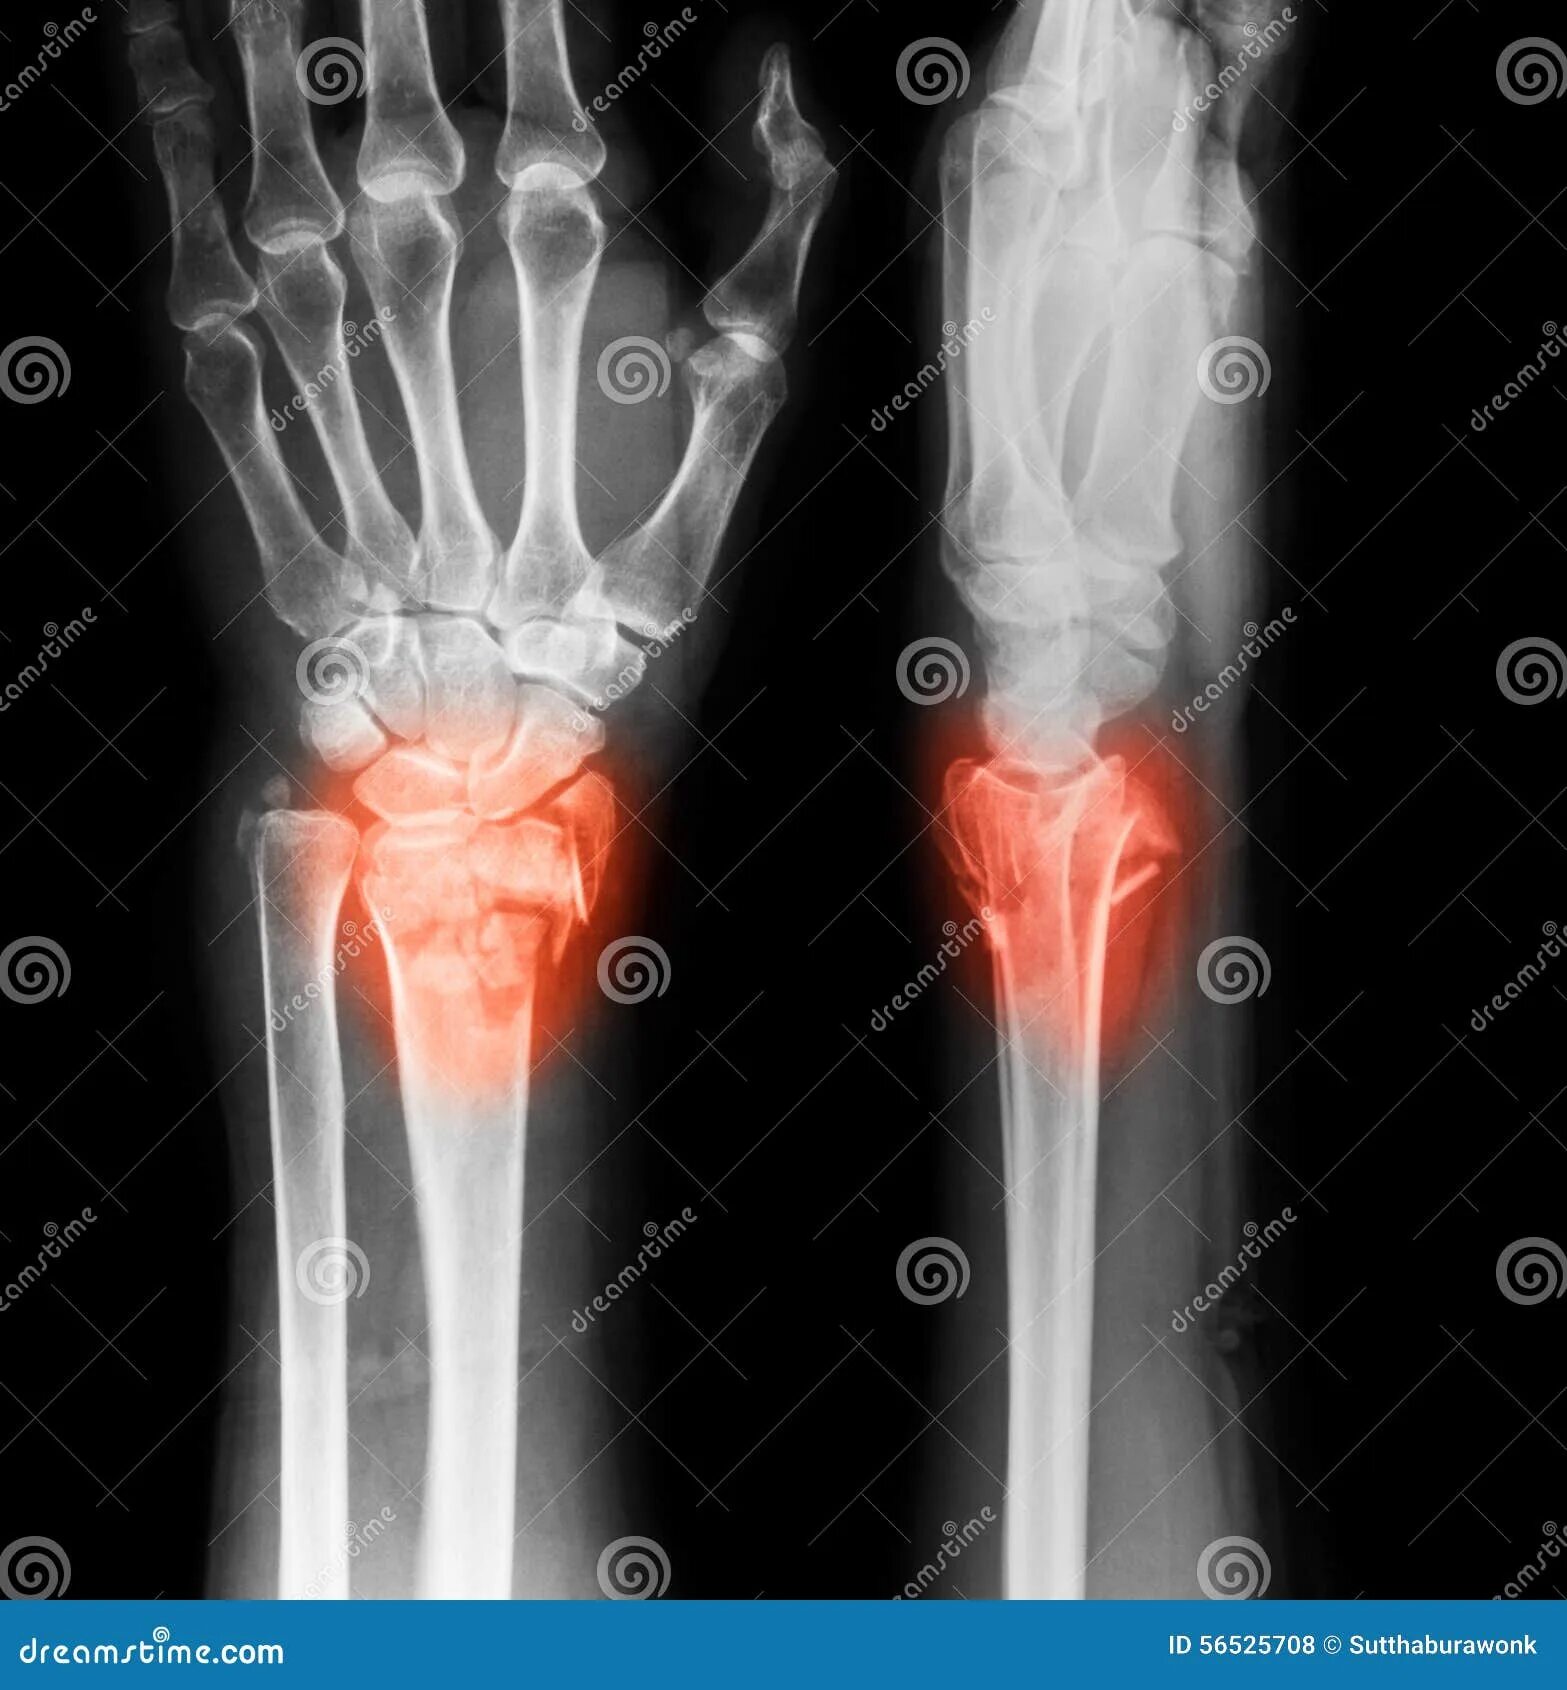

Артроз лучезапястного сустава 2 степени